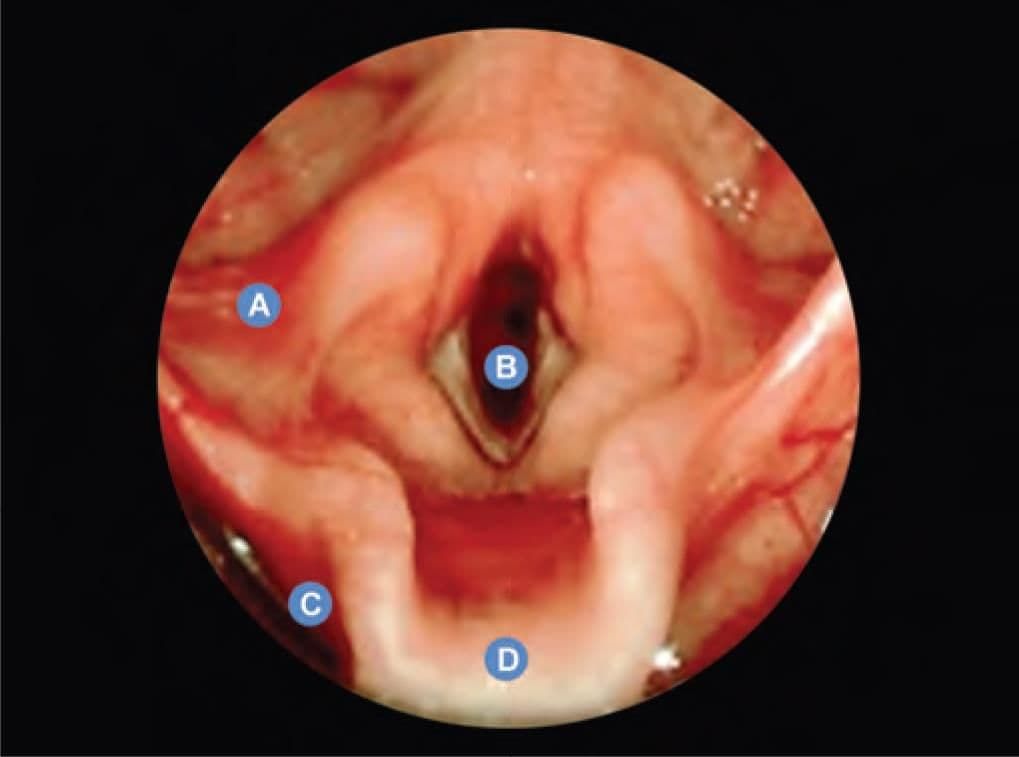

Which of the following marked structures does NOT constitute skeletal framework of larynx? (INI-CET Nov 2020)

Detailed Solution for Test: Anatomy - 3 - Question 20

Marker ‘A’ indicates the hyoid bone, which does not form part of the laryngeal skeleton. Marker B refers to the thyroid cartilage. Marker C denotes the epiglottis, a leaf-shaped cartilage that acts as a lid over the larynx. Marker D represents the cricoid cartilage (lamina). The laryngeal skeleton comprises nine cartilages:

• Unpaired (midline): thyroid cartilage, cricoid cartilage, epiglottis.

• Paired: arytenoid, corniculate, and cuneiform.

The hyoid bone is not included in the larynx, although the larynx is suspended from the hyoid.